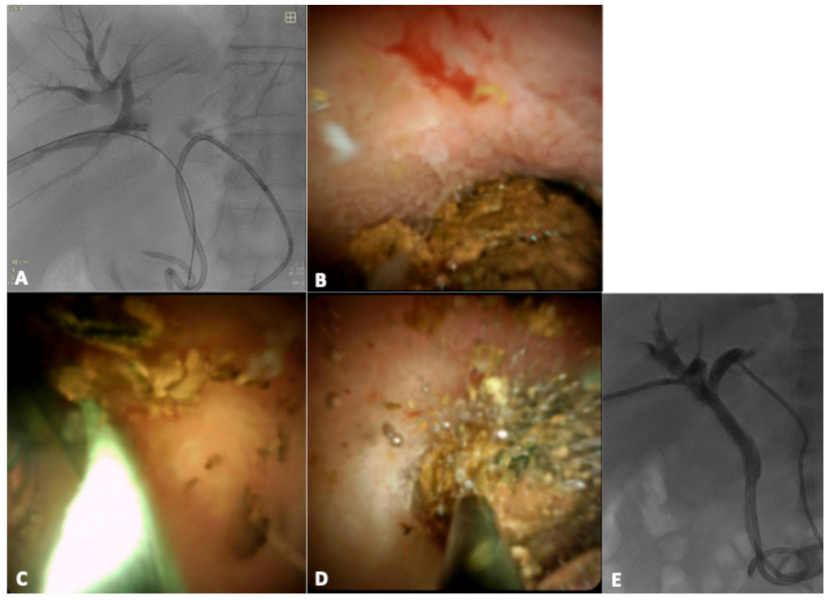

2.1. Patient 1

2.2. Patient 2

2.3. Technique and Procedure

3. Results